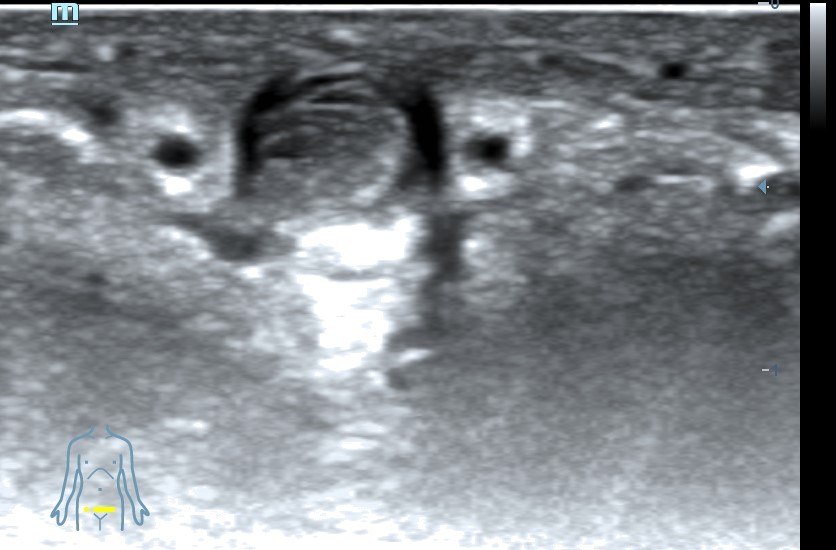

Ecografía clínica pene: se visualiza vena dorsal rellena de material hipoecogénico heterogéneo, no compresible, no flujo con Doppler color.

Diagnóstico: Trombosis vena dorsal del pene.